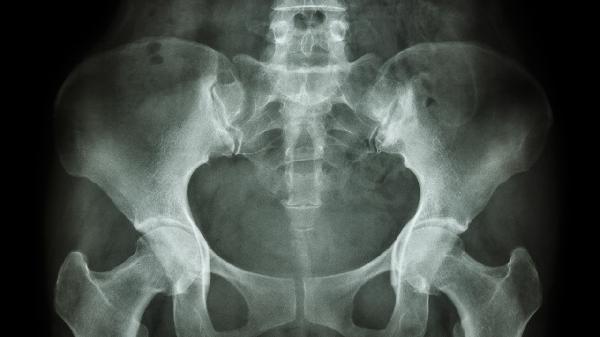

耻骨直肠肌综合征有哪些症状

耻骨直肠肌综合征主要表现为排便困难、肛门坠胀感、排便不尽感、会阴部疼痛及排便时间延长等症状。该疾病通常与盆底肌功能紊乱、慢性炎症刺激、局部外伤史、长期便秘或心理因素有关。